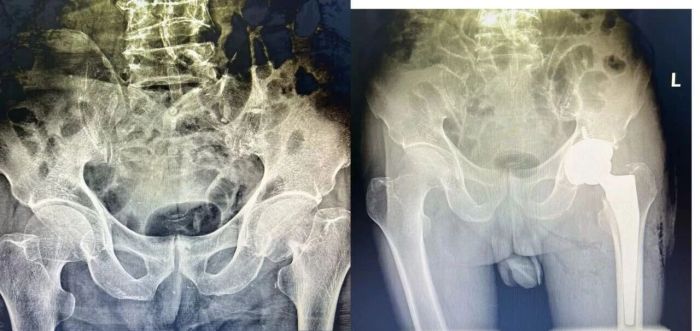

而手术治疗可让患者尽快下床,从根源上规避卧床风险。目前老年髋部骨折手术已日趋成熟,中心针对高龄高危患者,通过多学科评估制定个性化方案,优化麻醉方式降低风险。82岁的张大爷摔倒致股骨颈骨折,家属起初顾虑手术,经诊疗团队沟通后同意手术,术后第2天即可借助助行器下床,两周顺利出院,如今已能自主生活,此类案例在中心屡见不鲜。